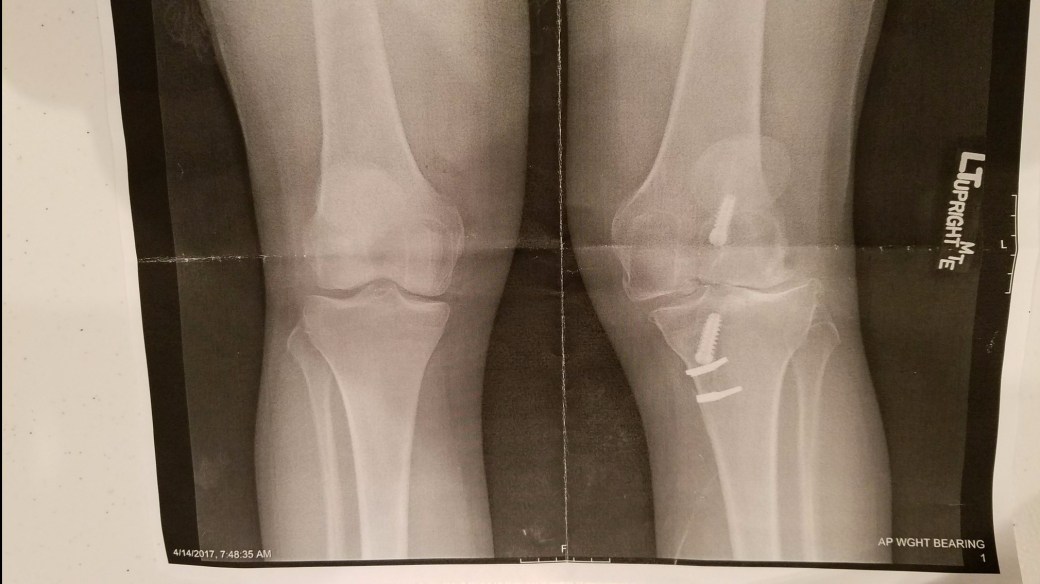

2017 was a year of me just trying to stay above water with waves crashing all around me. There were days where the darkness consumed my thoughts and I just wasn’t sure how I was supposed to keep moving. However, there were so many positives in 2017 too such as my daughter turning eight, our family vacation to the Valley Fair, our travels to Bottineau, my daughters track, basketball and now swimming events, bonfires with the neighbors, epic open mic nights of Rock Band in our basement, catching up with great friends at coffee shops, amazing concerts, and numerous family movie nights and that is just to name a few. Did I really want 2017 to be over? The answer is no, I wanted the horrible doctor appointments, the poking and prodding, numerous surgeries, the sleepless nights, awful medications, being away from my family, and the word CANCER to go away. What does 2018 have in store for me?

2017 was a year of me just trying to stay above water with waves crashing all around me. There were days where the darkness consumed my thoughts and I just wasn’t sure how I was supposed to keep moving. However, there were so many positives in 2017 too such as my daughter turning eight, our family vacation to the Valley Fair, our travels to Bottineau, my daughters track, basketball and now swimming events, bonfires with the neighbors, epic open mic nights of Rock Band in our basement, catching up with great friends at coffee shops, amazing concerts, and numerous family movie nights and that is just to name a few. Did I really want 2017 to be over? The answer is no, I wanted the horrible doctor appointments, the poking and prodding, numerous surgeries, the sleepless nights, awful medications, being away from my family, and the word CANCER to go away. What does 2018 have in store for me? I am not sure I get excited for a new year anymore as it means that life is passing by and all the beautiful memories are now just in the past. This is what we call life and we do our best to keep moving and to keep the light switch on. I love watching my daughter grow up as children I believe are there to make us stop and enjoy the little moments. She has this light inside of her that I hope the world will never burn out. I would like 2018 to not bring so much pain for those around me and to bring peace no matter what that looks like. Maybe I will get to jump out of a plane or travel more? Maybe I will get another tattoo? Maybe I will get to see some family and friends that I haven’t in a long time? Maybe I will just be? This is My New Year….